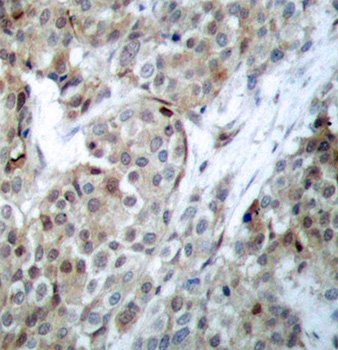

• AP0143: image 2

Immunohistochemical analysis of paraffin-embedded human breast carcinoma tissue using Phospho-Bad-S112 antibody.